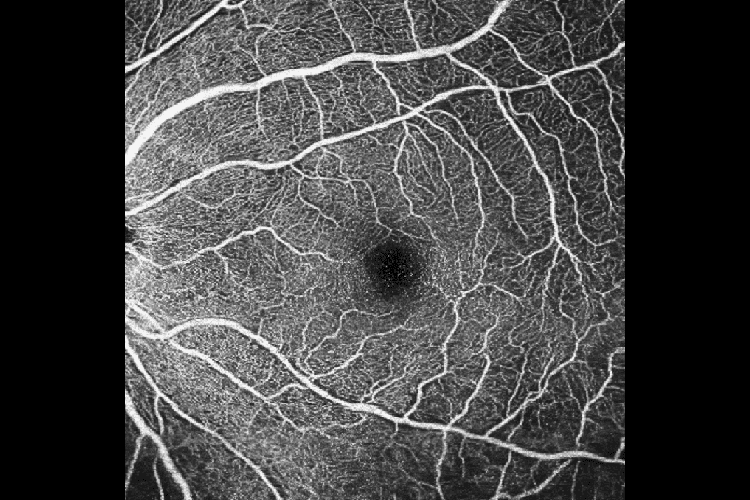

ОКТ Ангіографія з ANGIO Expert

Це додаткове програмне забезпечення використовує складні алгоритми для отримання інформації про рух із томограм, отриманих OCT-R1. Воно дозволяє візуалізувати навіть найдрібніші кровоносні судини як у 2D, так і в 3D форматах. Поєднання Xephilio OCT-R1 із програмним забезпеченням ANGIO Expert надає фахівцям потужний інструмент для візуалізації та аналізу мікроциркуляторного русла сітківки з винятковою деталізацією та точністю. ANGIO Expert також має технологію Intelligent Denoise, технологію штучного інтелекту, яка покращує зображення оптичної когерентної томографії ангіографії (ОКТА), зменшуючи шум зображення, покращуючи деталі та покращуючи видимість за лічені секунди, а також здатність створювати панорамні зображення, поєднуючи 4–5 сканувань ОКТА, що допомагає візуалізувати патології сітківки на дальній периферії.

Функція інтелектуального усунення шумів Canon на основі штучного інтелекту пропонує нову якість зображень ОКТА на основі лише одного сканування – без необхідності отримувати та об’єднувати кілька зображень. Технологія Canon Deep Learning — це революційна технологія, яка базується на величезних обсягах клінічних даних для отримання зображень із значно зменшеним шумом зображення, підвищеною деталізацією та покращеною видимістю всього за кілька секунд.